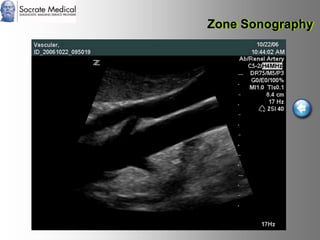

Il documento presenta la tecnologia della zone sonography, che promette una rivoluzione nel campo degli ultrasuoni, superando i limiti dei sistemi tradizionali grazie a metodi di acquisizione dati più veloci e una gestione delle informazioni migliorata. Questa tecnologia consente una maggiore definizione dell'immagine, una riduzione degli artefatti e un'ottimizzazione del processo diagnostico, con vantaggi in termini di tempo e costi. Inoltre, il channel domain processing e la zone speed technology offrono applicazioni avanzate e miglioramenti nella sicurezza diagnostica.